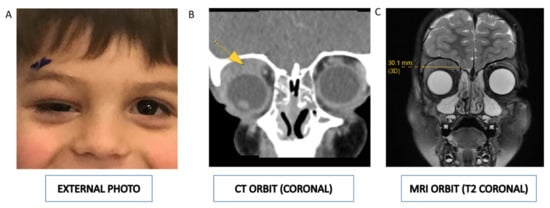

| 8 | 4yrs | M | USA | Superior | R | Eyelid swelling; hypoglobus; ocular motility deficit | None | Orbital mass biopsy; peripheral blood smears; bone marrow aspirate smears; flow cytometry; UCSF500 molecular test (next generation sequencing) |